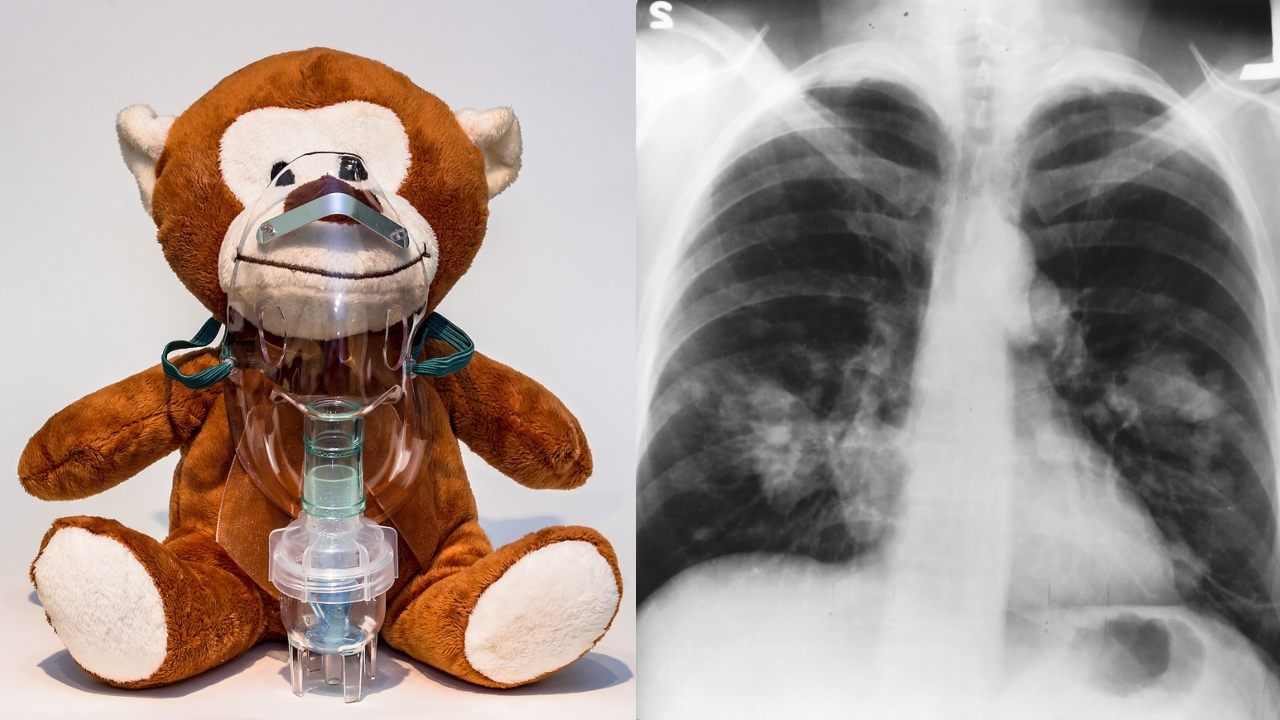

Las nebulizaciones son de gran ayuda para limpiar los pulmones y suelen ser recomendadas para personas con determinados padecimientos de las vías respiratorias como sinusitis, asma, EPOC, fibrosis quística, y hasta para las molestias del resfriado común. Si necesitas realizar este tratamiento, pero te resultan demasiado costosas las máquinas que venden en lugares especializados, puedes hacer tu propio nebulizador casero.

Podrías preguntarte cómo es esto posible. Pues en realidad, un nebulizador tiene como función la de convertir el medicamento líquido en vapor para hacerlo llegar a los pulmones, lo cual abre las vías respiratorias ayudando al paciente a respirar mejor, además de eliminar las flemas y aliviar la tos.